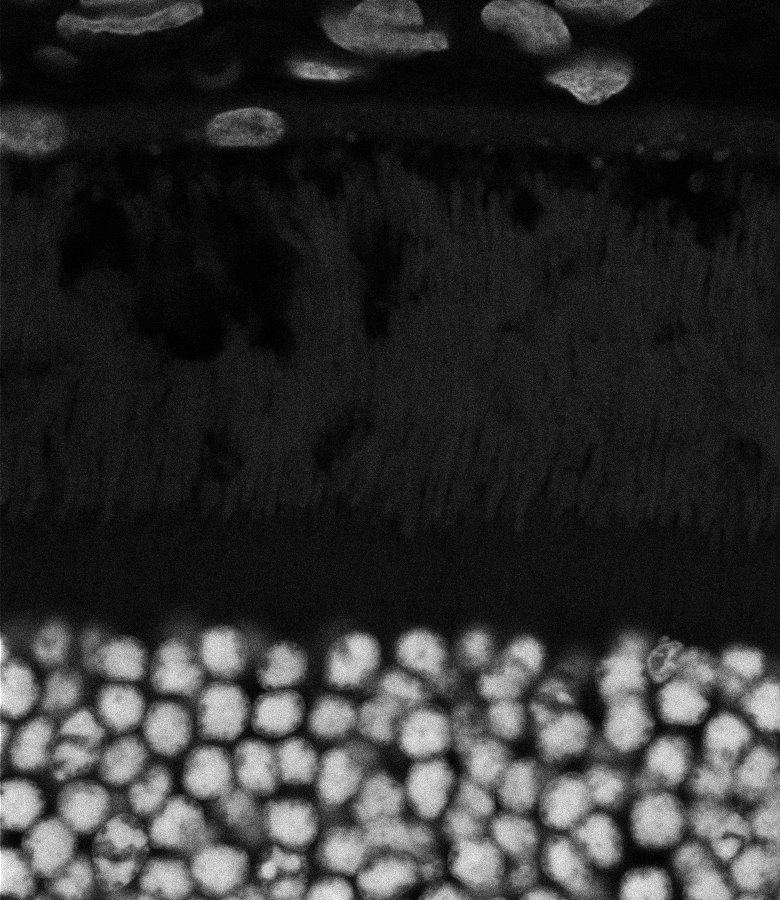

Healthy Eye

Blast Eye